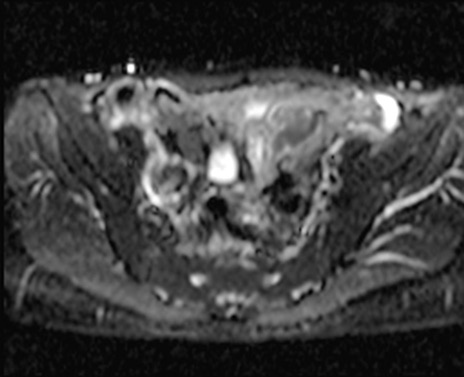

症例39 DWI/ADC

MRI(4日後)